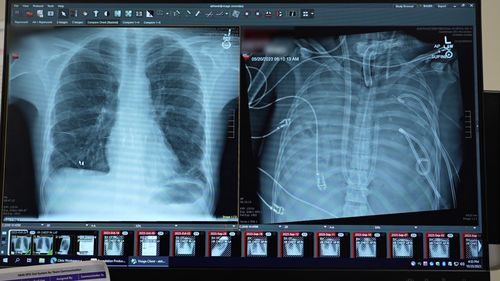

The patients’ new lungs (left) and old lungs (right). (Northwestern Medicine)